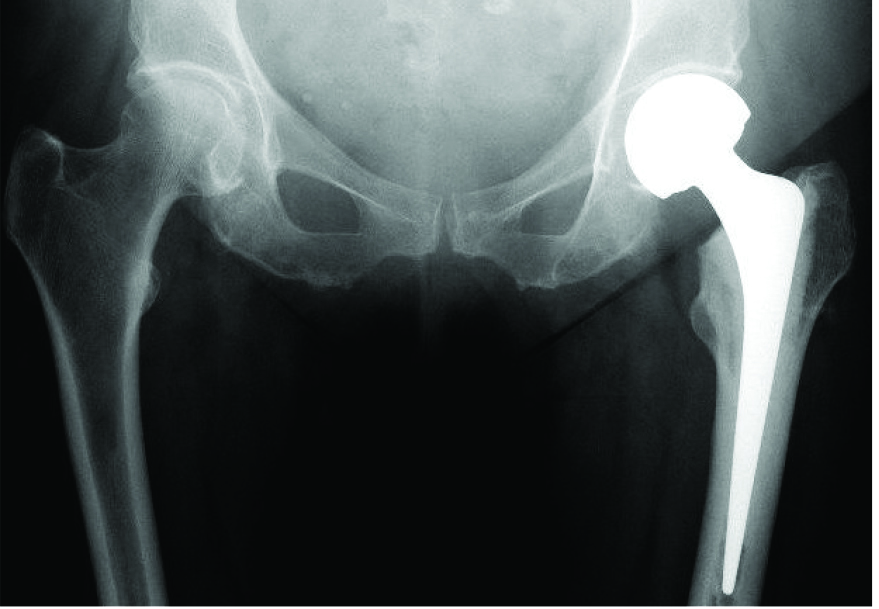

This is a total hip replacement

This is a partial hip replacement

If the fracture is in the neck of the femur, the blood supply to the head of the femur will be compromised, and a partial or total hip replacement will be necessary.